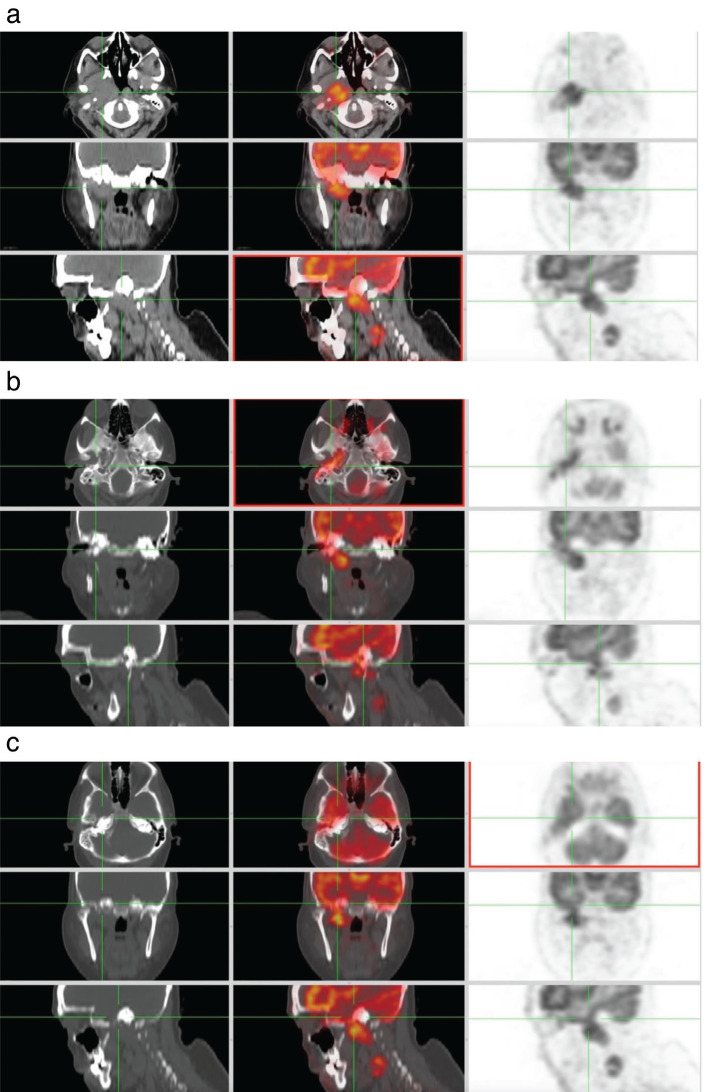

We report the case of a 56-year-old female recently diagnosed with well-differentiated squamous cell carcinoma of the external auditory canal. The patient underwent an 18F-fluorodeoxyglucose positron emission tomography/computed tomography for staging assessment. This examination revealed intense uptake in the right ear canals, tympanic cavity, eustachian canal, parapharyngeal area, and infratemporal fossa. Notably, we identified intracranial dural metastasis, which represents an uncommon site for metastatic spread in general.